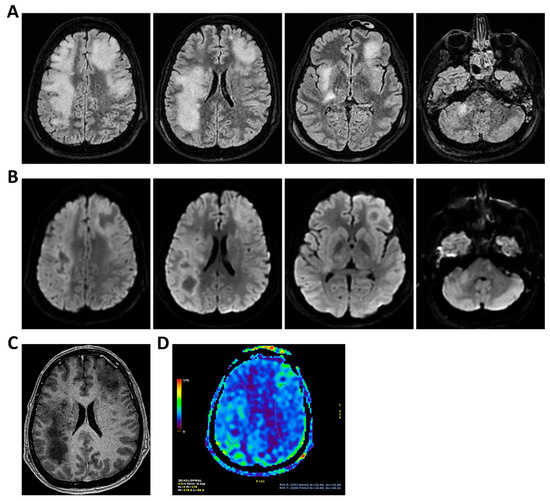

Background: Meningoencephalitis is a complex inflammatory condition of the CNS that can result in significant morbidity and mortality in critically ill adults. Accurate and timely neuromonitoring is essential for guiding management and improving outcomes. This study aimed to descriptively evaluate the prognostic value of early TCCD monitoring, particularly the pulsatility index, and its integration with conventional and perfusion MRI in patients with meningoencephalitis. Methods: We present an observational, retrospective, cohort study involving ten adult patients (median age 56 years, IQR 45.5–68.5; mean 55.9, range 35–76) with neurological syndromes caused by suspected or confirmed infectious meningoencephalitis. Etiologies included bacterial meningitis/meningoencephalitis (50%), viral meningoencephalitis (10%), neurotoxoplasmosis (10%), progressive multifocal leukoencephalopathy (10%), and undetermined origin (20%). Patients underwent TCCD and MRI within 24 h. In five cases, standard MRI sequences were acquired, while in the remaining five, perfusion imaging was performed using Arterial Spin Labelling (ASL). A favorable outcome was defined as survival with neurological recovery (Glasgow Outcome Scale > 5) at ICU discharge. Results: TCCD-derived PI provided valuable information on cerebral hemodynamics. PI values ≤ 1.25 were associated with favorable clinical outcomes and symmetrical MRI findings. Conversely, PI > 1.25 correlated with poor prognosis and often preceded MRI-detectable structural damage. When combined with ASL, PI mirrored the detected perfusion asymmetries and was associated with poor prognosis in fatal cases. Conclusions: Bedside TCCD can offer real-time assessment of cerebrovascular dynamics and, when integrated with conventional and ASL MRI, could enhance the understanding of pathophysiological processes in meningoencephalitis, supporting timely and informed decisions in neurocritical care.